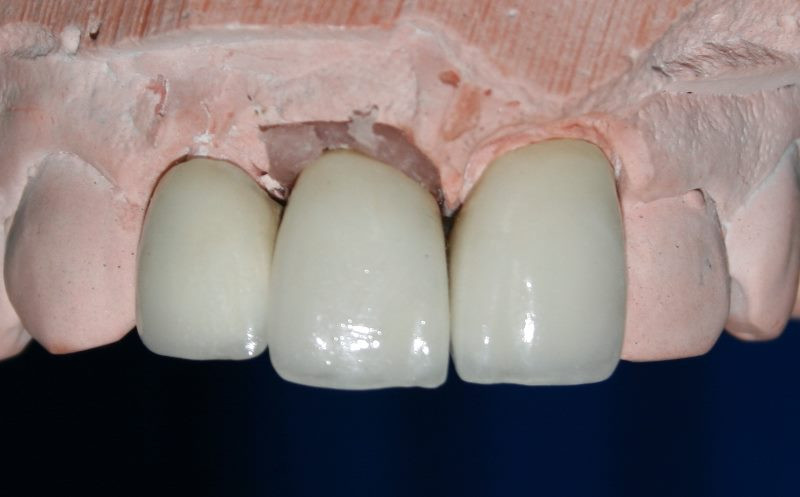

Trabajo de laboratorio dental

Se prepara para toma de impresión (modelo)